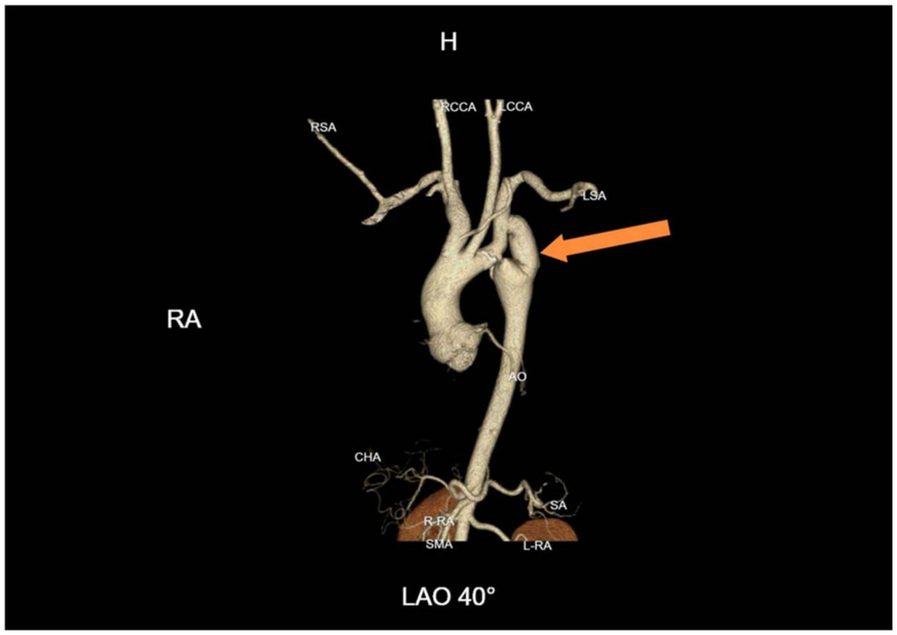

After more than six months of follow-up observation, the patient reported complete resolution of cardiopulmonary and neurological symptoms. Blood pressure remained well controlled, and there was no recurrence of symptoms. Serial imaging demonstrated continued graft patency without evidence of complications such as graft occlusion, pseudoaneurysm, infection, or aneurysmal progression (Figure 4). Additional axial CTA images are provided (Figure 5) to better illustrate the extent of aortic calcification.

Figure 4

One-year follow-up CTA demonstrating graft patency. Continued patency of the bypass graft with no evidence of pseudoaneurysm, graft occlusion, or aneurysmal progression at the coarctation site.